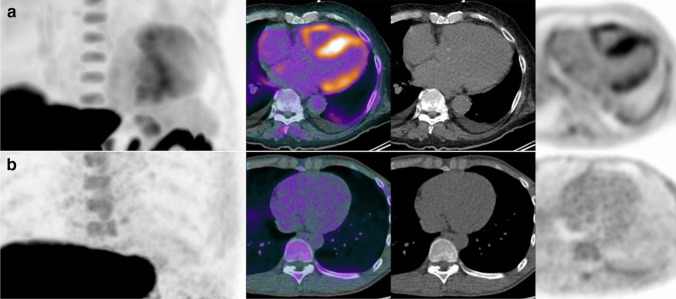

越来越多的人认识到心脏淀粉样变性(CA)是心力衰竭的一个原因,加上治疗方案的进步,强调了早期发现的必要性。正电子发射断层扫描(PET)成像是一种很有前途的诊断和治疗CA的非侵入性工具。本文综述了目前PET成像技术的全面分析,重点是放射性示踪剂,包括[11C]匹兹堡化合物B, [18F]氟替他莫,[18F]Florbetapir, [18F]Florbetaben, [18F]氟化钠和[124I]Evuzamitide。PET成像鉴别CA亚型和量化淀粉样蛋白负担的能力有助于确定预后并有助于监测治疗反应。然而,标准化成像方案和建立明确的诊断阈值仍然具有挑战性。随着PET成像的不断发展,它有望通过促进CA的早期诊断、更准确的亚型区分和更好的治疗监测来改善患者的预后。

The increasing recognition of cardiac amyloidosis (CA) as a cause of heart failure, coupled with advancements in therapeutic options, has underscored the need for early detection. Positron emission tomography (PET) imaging emerged as a promising non-invasive tool for diagnosing and managing CA. This review provides a comprehensive analysis of current PET imaging techniques, focusing on radiotracers, including [11C]Pittsburgh Compound B, [18F]Flutemetamol, [18F]Florbetapir, [18F]Florbetaben, [18F]-sodium fluoride, and [124I]Evuzamitide. PET imaging's ability to differentiating CA subtypes and quantify amyloid burden contributes defining prognosis and aids in monitoring treatment response. However, standardizing imaging protocols and establishing definitive diagnostic thresholds remain challenging. As PET imaging continues to evolve, it promises to improve patient outcomes by facilitating earlier diagnosis, more accurate subtype differentiation, and better treatment monitoring in CA.